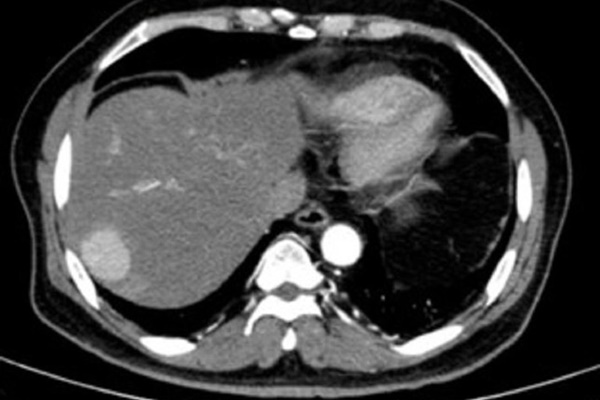

Hình ảnh kiểm tra phát hiện khối ung thư nằm vị trí sát rìa gan của người bệnh

Bác sĩ Hàng Thế Cơ, Khoa Ngoại Tổng Quát bệnh viện này cho biết, khối u gan nằm ở vị trí hạ phân thùy VII của bệnh nhân có kích thước 33x35 mm. Bệnh nhân được sinh thiết khối u dưới hướng dẫn siêu âm và chẩn đoán xác định là ung thư gan nguyên phát. Sau chẩn đoán, bệnh nhân đã được chỉ định cắt phần gan có khối ung thư. Cuộc mổ diễn ra thuận lợi, sau phẫu thuật sức khỏe người bệnh đã bình phục tốt. Nhờ phát hiện sớm nên khối chưa gây ảnh hưởng đến sức khỏe của người bệnh.